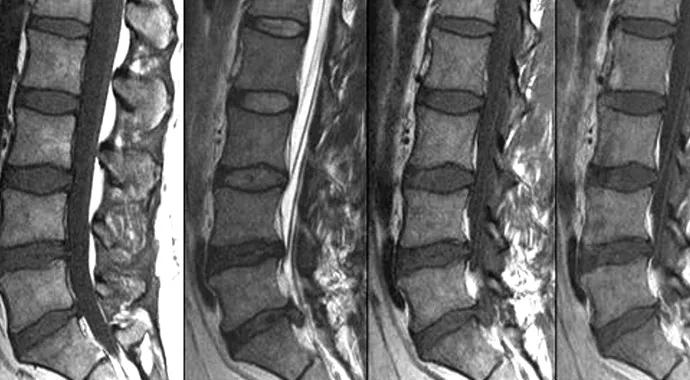

• Scenario 2 involved a recurrent L5-S1 herniated disk following two microdiskectomies (Figure).

Figure. The case vignette (with associated radiographs and MRIs) that was presented as Scenario 2 in the survey. Reprinted from reference 1 (Mroz et al) with permission from Elsevier.